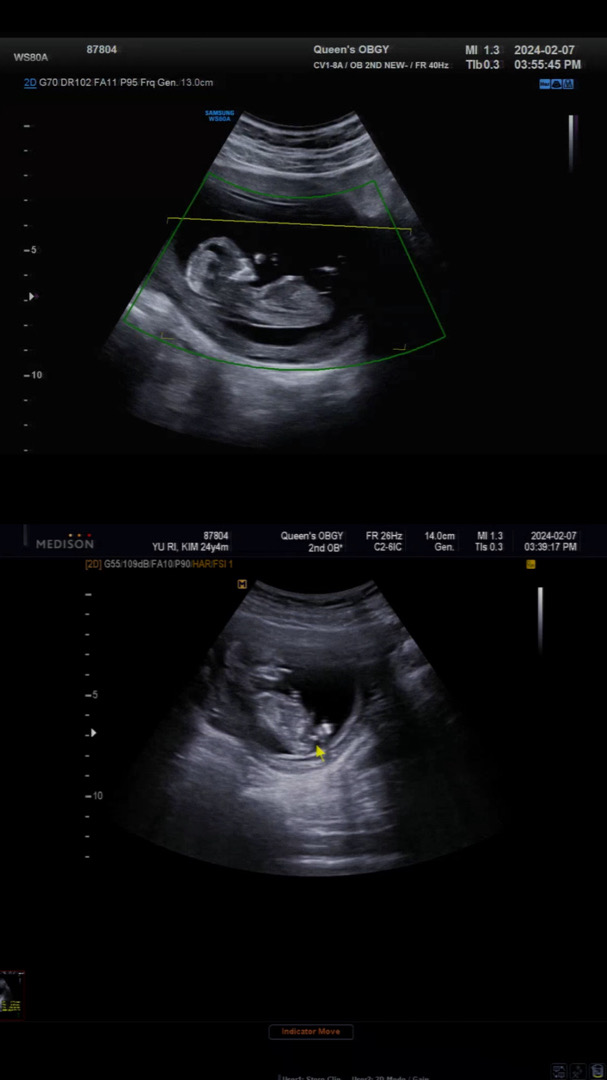

음..초음파상 뭔가 살짝 보이는게..아들일 듯 합니디☺️

12주3일 성별

안녕하세요 글은 처음쓰네용 산부인과 근무중이라 저희병원 원장님께 진료 보고있어서 성별을 빨리 알려주셨습니다 확정은 아니고 아들같은데~? 이러셨는데 반전이 있을지 ..?

원장님도 저길 보면서 아들같은데~ 라하셨어요 🤣🤣🫢